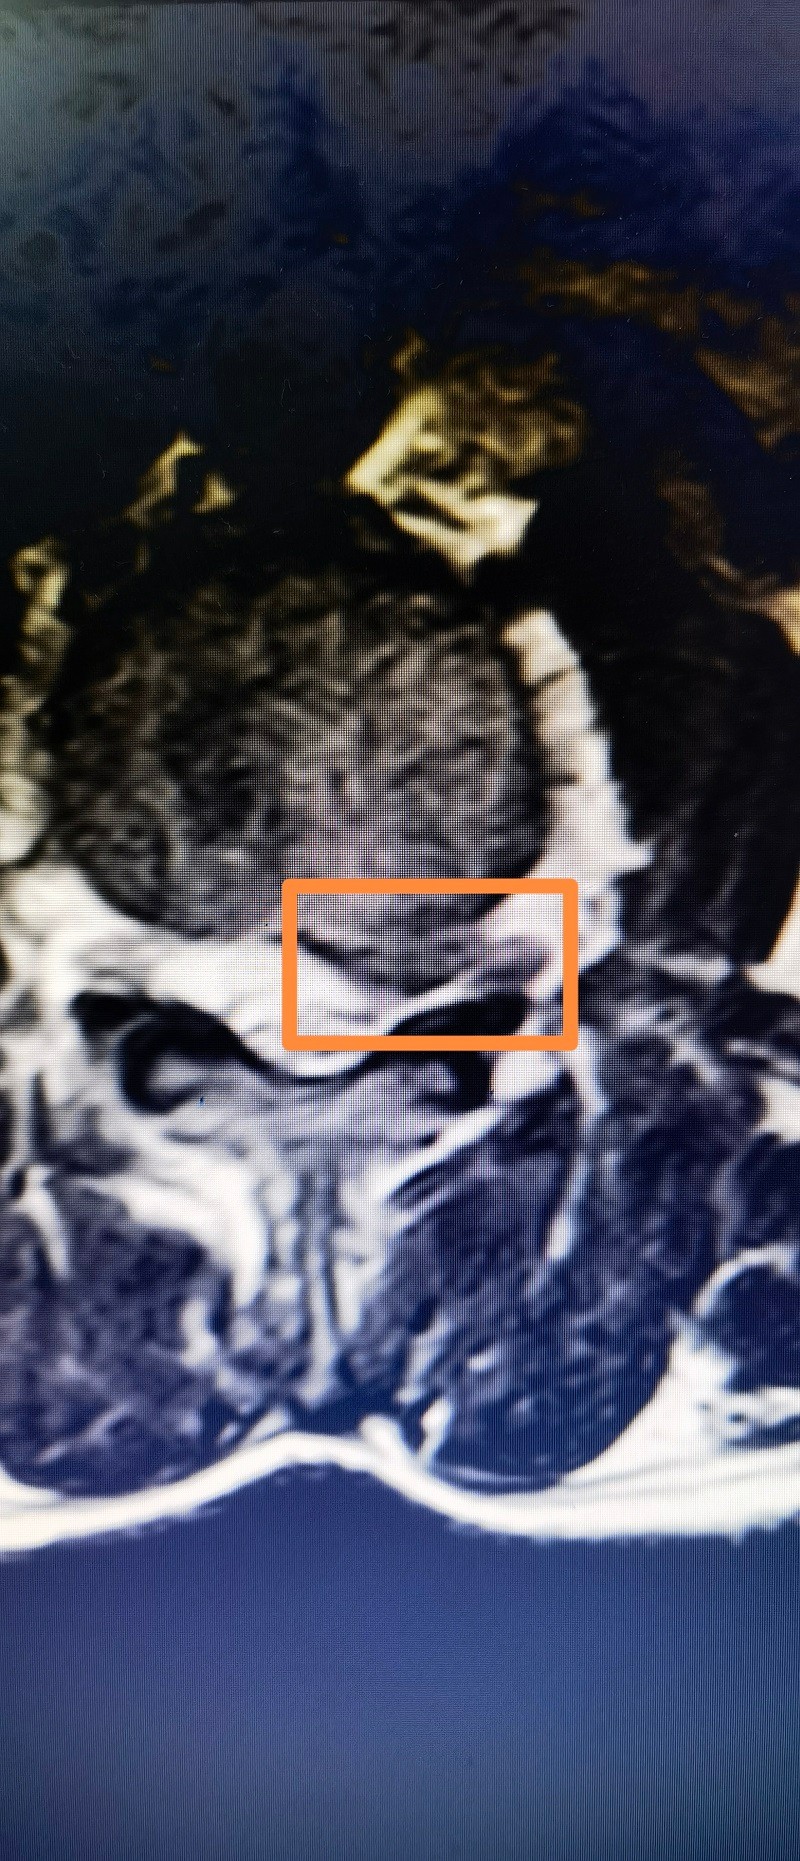

唐先生的术前MRI,腰3.4椎间盘左侧突出。医院供图